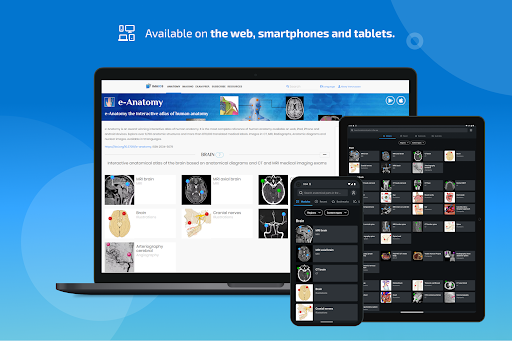

e-Anatomy didasarkan pada atlas daring IMAIOS e-Anatomy yang telah memenangkan penghargaan. Bawalah referensi anatomi manusia terlengkap, ke mana pun Anda pergi, di perangkat seluler atau tablet Anda.

HARGA aplikasi termasuk akses ke semua modul adalah 124,99$ per tahun. Langganan ini juga memberi Anda akses ke e-Anatomy di situs web IMAIOS.